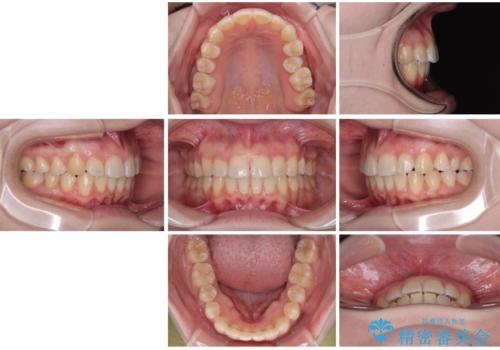

左上の前歯が出ているのが気になる 審美装置による非抜歯ワイヤー矯正

- 左上の前歯が出ていることを主訴として来院された患者様です。

当初はインビザラインを希望されていましたが、職業柄お茶する機会が多く装着時間を確保することが難しいとのことで、相談の上ワイヤー矯正の中では目立ちにくい審美装置で矯正を進めていくこととしました。

1年と少しで矯正治療を終えることができ患者様は大変満足されました。